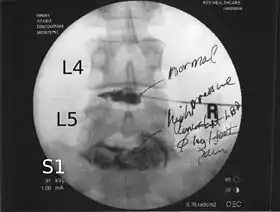

![]() Lumbar provocative discography showing a degenerated disc, L5-S1 with normal disc L4-L5 | |

Spinal MRI is the imaging of choice to investigate the spine and intervertebral discs.[1] Meanwhile, lumbar discography is used to demonstrate degeneration and herniation of lumbar intervertebral discs by injecting a dye into the nucleus pulposus of the discs. The procedure is also used to reproduce pain back pain for those who has such symptoms. Lumbar discography is also used to access the response of a subject to anaesthetic injection. Other uses includes: suspected discogenic pain without radicular sign (pain travelling to lower limbs along a dermatome), and confirmation of normal intervertebral discs above and below a site before spinal fusion.[1] However, evidence supporting the usefulness of lumbar discography in recognising intervertebral disc problems are limited.[1] There is no role for cervical or thoracic discography in diagnosing disc pathologies at the cervical or thoracic regions.[1][2]